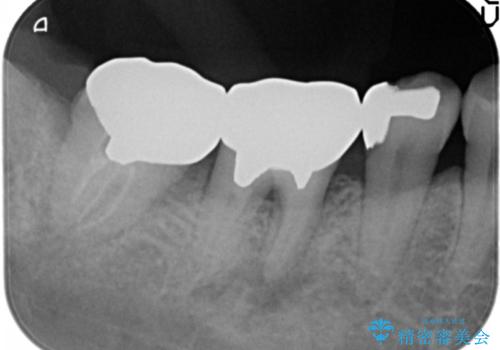

歯ぐきの腫れが治らない 石灰化した狭小根管治療

- 他院で根管治療を受け銀歯をかぶせるところまで行ったが、直後より腫れ・痛みが引かず当院へ相談、来院されました。

X線写真検査より根管充填の行われていない根管、視診より歯肉からの排膿路を認め、急性根尖性歯周炎の治療として根管再治療を計画します。

治療途中、マイクロスコープでも根管が追えないほど狭く細くなった根管へと変性しており根管の拡大形成が難しい状況でした。

CTを撮影し少しづつ丁寧に根管を探索することで無事根管再治療を行い、症状がなくなりました。